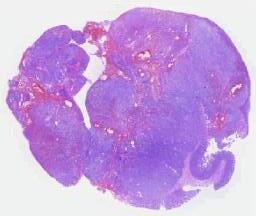

临床资料: 患者,女,34岁,病史:疑似“感冒”后咳嗽咳痰胸闷2周,影像CT:肺占位,生育史:孕3产3,一儿两女进行肺活检,两个月后心包多发结节,进行心包活检。